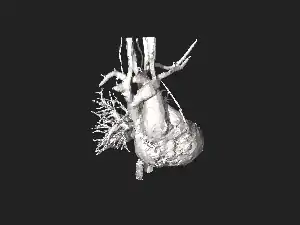

| Illustration depicting coarctation of the aorta | |

Aortic coarctation using different imaging techniques[10]

Aortic coarctation using different imaging techniques[10] Coarctation of the aorta

Coarctation of the aorta.jpg.webp) Coarctation of the aorta

Coarctation of the aorta.jpg.webp) Coarctation of the aorta

Coarctation of the aorta

Schematic drawing of alternative locations of a coarctation of the aorta, relative to the ductus arteriosus. A: Ductal coarctation, B: Preductal coarctation, C: Postductal coarctation. 1: Aorta ascendens, 2: Arteria pulmonalis, 3: Ductus arteriosus, 4: Aorta descendens, 5: Truncus brachiocephalicus, 6: Arteria carotis communis sinistra, 7: Arteria subclavia sinistra 3D model of coarctation of aorta

3D model of coarctation of aorta